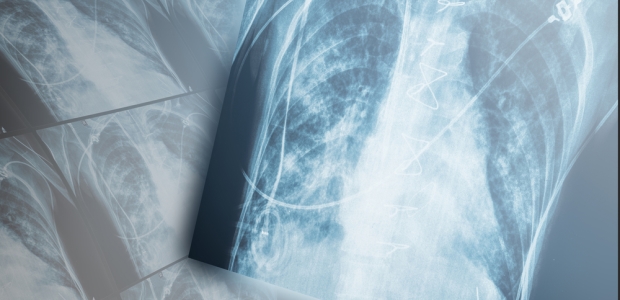

"Although much remains unknown regarding the toxicity of flavoring-related chemicals, employers and workers can take steps to address working conditions and work practices that place workers at risk," according to the agency. This obstructive lung disease can be severe: Lung biopsies revealed some workers in the industry suffer from constrictive bronchiolitis obliterans, which causes the smallest airways in the lung to become scarred and constricted, blocking the movement of air.

"The main respiratory symptoms experienced by workers affected by obliterative bronchiolitis include cough (usually without phlegm), wheezing, and worsening shortness of breath on exertion. The severity of the lung symptoms can range from only a mild cough to severe cough and shortness of breath on exertion. These symptoms typically do not improve when the worker goes home at the end of the workday or on weekends or vacations. Usually these symptoms are gradual in onset and progressive, but severe symptoms can occur suddenly. Some workers may experience fever, night sweats, and weight loss. Before arriving at a final diagnosis, doctors of affected workers initially thought that the symptoms might be due to asthma, chronic bronchitis, emphysema, pneumonia, or smoking," NIOSH reported on this page.

The agency says affected workers should be promptly referred for further medical evaluation if they have a persistent cough; persistent shortness of breath on exertion; frequent or persistent symptoms of eye, nose, throat, or skin irritation; abnormal lung function on spirometry testing; or accelerated decline in lung function. "Physicians should advise workers about any suspected or confirmed medical condition that may be caused or aggravated by work exposures, about recommendations for further evaluation and treatment, and specifically about any recommended restriction of the worker's exposure (including removal from the workplace) or use of personal protective equipment. To date, most cases have shown little or no response to medical treatment. Affected workers generally notice a gradual reduction or cessation of cough years after they are no longer exposed to flavoring vapors, but abnormalities on lung function tests and shortness of breath on exertion persist. Several with very severe disease were placed on lung transplant waiting lists. Workers exposed to flavorings may also experience eye, nose, throat, and skin irritation. In some cases, chemical eye burns have required medical treatment. While most workers with very severe flavoring-related lung disease have shown evidence of bronchiolitis oblliterans, it is possible that some workers exposed to flavoring chemicals may develop new-onset asthma or exacerbation of pre-existing asthma."